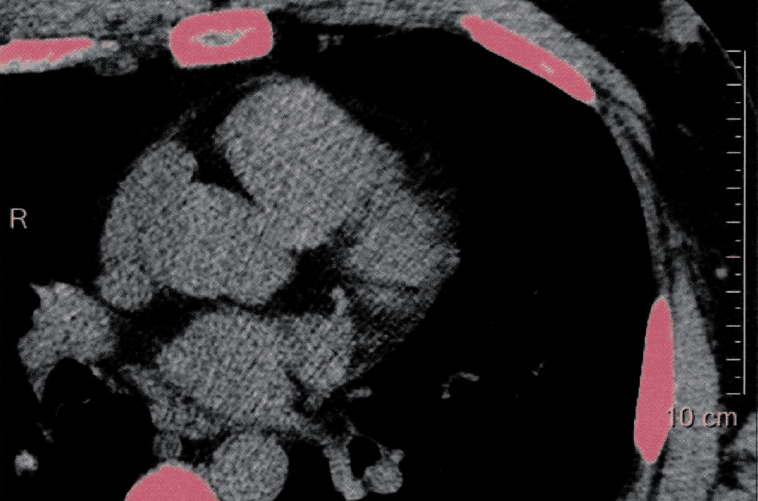

The patient has a total Calcium Score of 0. This places the patient into the 0th percentile in comparison to a group of patients asymptomatic for coronary artery disease with the same age and gender. This means that 0% of males aged 40-44 have calcium scores lower than the patient. Coronary artery calcification is a specific marker for coronary atherosclerosis. The amount of calcification correlates with the severity of coronary atherosclerosis. A score of 0 implies a low likelihood of coronary obstruction, but cannot totally exclude the presence of atherosclerosis. A high score indicates a significant plaque burden and relative risk for future cardiovascular events. It should be understood that calcification is not site specific for stenosis but rather indicates the extent of atherosclerosis in the coronary arteries overall. There was no identifiable plaque detected. Patient is advised to adhere to general guidelines on diet and exercise.I’ll ignore the “general guidelines on diet” part, thank you very much =) If you’re curious and would like to see the full content of my CAC report, you can check that out here.